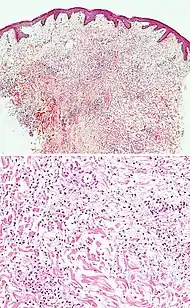

| Kaposi’s sarcoma in patch stage | The patch stage typically shows irregular proliferation of jagged vascular channels in the dermis below an integral epidermis. The so-called promontory sign is sometimes found in patch stage lesions and denotes vascular spaces surrounding pre-existing blood (see image).[23]

vessels |

![]() |